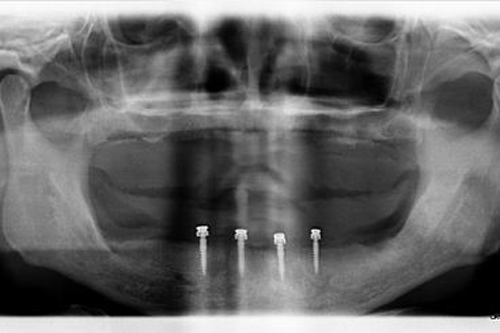

Pterygoid Dental Implants are a specific type of dental implants that are used for full-mouth rehabilitation in patients with insufficient bone volume in the upper jaw. They are named ‘Pterygoid’ because they are placed in the pterygoid plate, which is part of the sphenoid bone at the back of the upper jaw.

Pterygoid Implants are longer than conventional implants, typically measuring between 15 to 20 millimeters. Their increased length provides added stability and allows them to harness support from the dense pterygomaxillary region, eliminating the need for sinus lift procedures or bone grafts, which are often required with other types of implants. Thus, they offer a viable and effective solution for patients who have been told they are not suitable candidates for traditional implants due to lack of bone mass.

As Pterygoid Dental Implants are anchored in the pterygoid plates, they provide a firm and stable foundation for prosthetic teeth, ensuring optimal functionality and appearance.